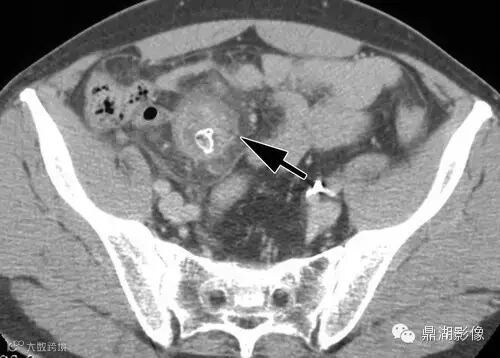

49岁男性,腹痛,恶心,呕吐,厌食。盆腔右侧可见圆形液体积聚(箭),内见钙化的肠石,邻近脂肪炎性改变。